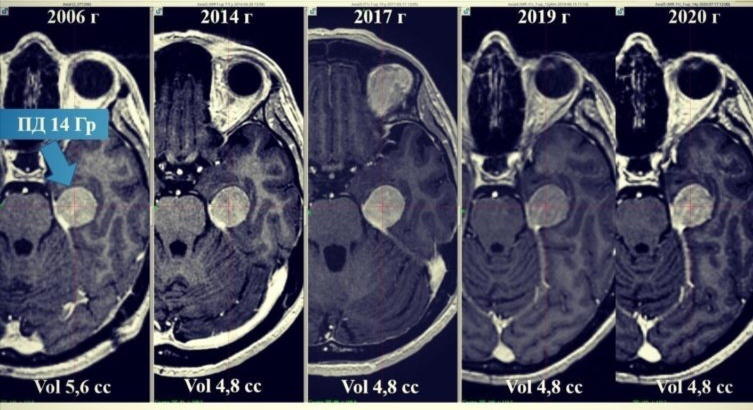

14 лет после Гамма-ножа: что стало с менингиомой?

14 лет после радиохирургии в предписанной дозе 14 Гр. За 14 лет отмечается незначительное уменьшение объёма опухоли и ее стабильное состояние.